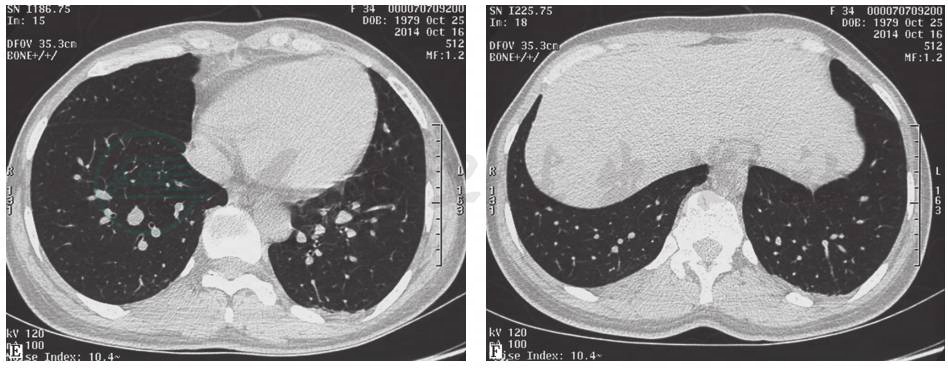

(一)临床信息

肺动脉增强CT(2015年3月20日):肺动脉宽3.5cm,肺动脉主干左侧内壁略毛糙,可见点状充盈缺损区(图8)。与2015年1月6日胸部CT相比,左肺下叶有新出现的多发病灶,原多发感染病灶大部分有所吸收,原右侧胸腔积液吸收(图9)。

超声心动图(2015年3月24日):根据影像学检查提供的信息,再次行超声心动检查,发现动脉导管开口对侧肺动脉壁有黄豆大小赘生物,随血流漂动(图10)。

图8 肺动脉增强CT表现(2015-03-20)

图9 胸部CT表现(2015-03-20)

图10 超声心动图

引自:主编:.呼吸系统疑难病例诊疗辨析.第1版.ISBN:978-7-117-26415-0